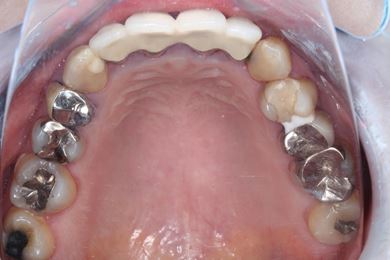

インプラント治療+セラミック治療

| 治療内容 | インプラント3本、ジルコニアフレームオールセラミッククラウン7本(ジルコニア用土台1本)、メタルボンドセラミッククラウン3本(メタルボンド用土台3本)、ハイブリッドセラミッククラウン3本、ハイブリッドセラミックインレー3本 | ||||||||||||||||||||||||||||||||